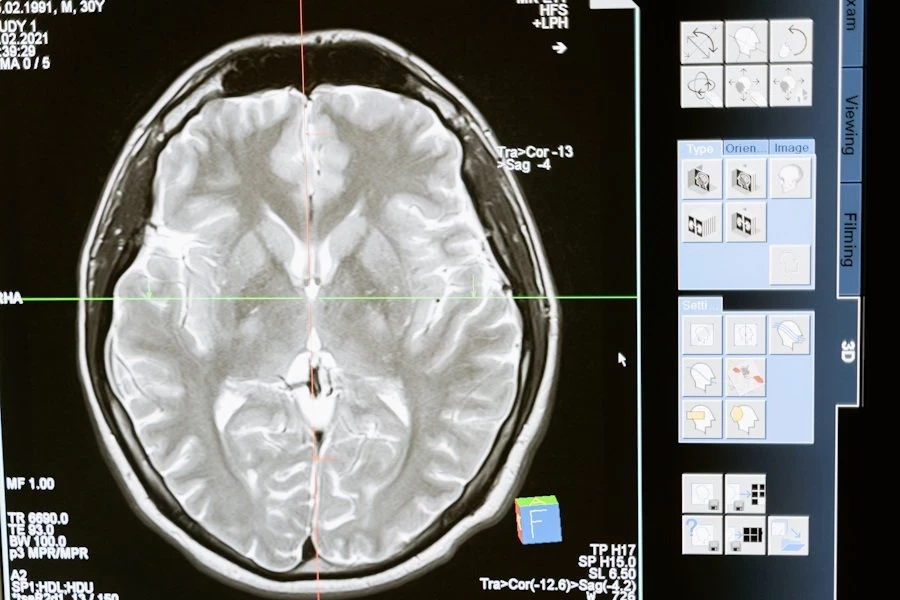

Ученые из University of Texas at Austin разработали инновационные текучие чернила для электроэнцефалографии (ЭЭГ). Этот метод исследования активности мозга стал не только точнее, но и комфортнее для пациентов.